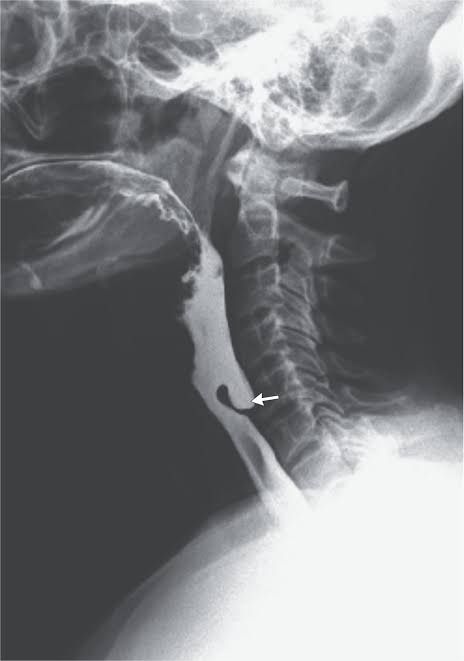

The patient suffered severe pain and difficulty in swallowing, and was not eating solid food for the last two years. Achalasia cardia is a chronic condition in which the muscle at the base of the throat where food enters the stomach is too tight. This can cause food and liquids to back up in the throat.

Zenker’s diverticulum develops when the muscle between the throat and oesophagus becomes narrow and tight, causing the throat area to resemble a pouch. Over time, the pouch can enlarge as the muscles below it tightens further. Chewed food particles can get caught in this pouch causing a serious obstruction.